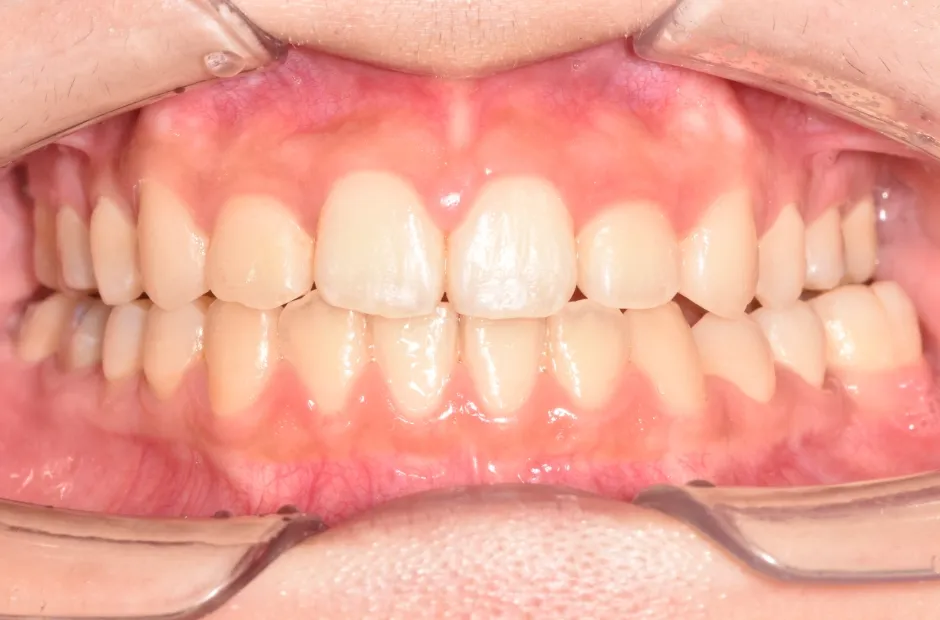

過剰歯

| 診断名・主訴 | でこぼこ |

|---|---|

| 年齢・性別 | 22歳・女性 |

| 治療期間・回数 | 1年6か月 |

| 治療に用いた主な装置 | リンガルブラケット |

| 抜歯部位 | 過剰歯 |

| 治療費 | 100万円(税抜) |

| リスク・副作用 | 装置による違和感・疼痛・歯肉退縮・歯根吸収・虫歯のリスクなど |

治療前